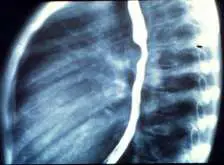

2個月大的女嬰,出生後不久即被發現呼吸急促合併喘鳴聲( stridor ),氣管鏡檢查發現氣管狹窄,食道攝影如圖所示。下列何者為最可能的診斷?

本題附圖為側位(lateral view)食道鋇劑攝影(barium esophagram)。圖中可見鋇劑充填的食道,在氣管隆突(carina)水平處的食道前壁出現明顯的壓迫性凹陷(anterior indentation),食道後壁未見明顯壓迫。此一「前方壓迫、無後方壓迫」的影像特徵,是肺動脈吊帶(pulmonary artery sling)的病理特徵影像(virtually pathognomonic finding)。

- 肺動脈吊帶(pulmonary artery sling):左肺動脈異常起源於右肺動脈後方,走行於氣管後壁與食道前壁之間,因此只產生食道前方壓迫,不造成後方壓迫,此點為鑑別關鍵。